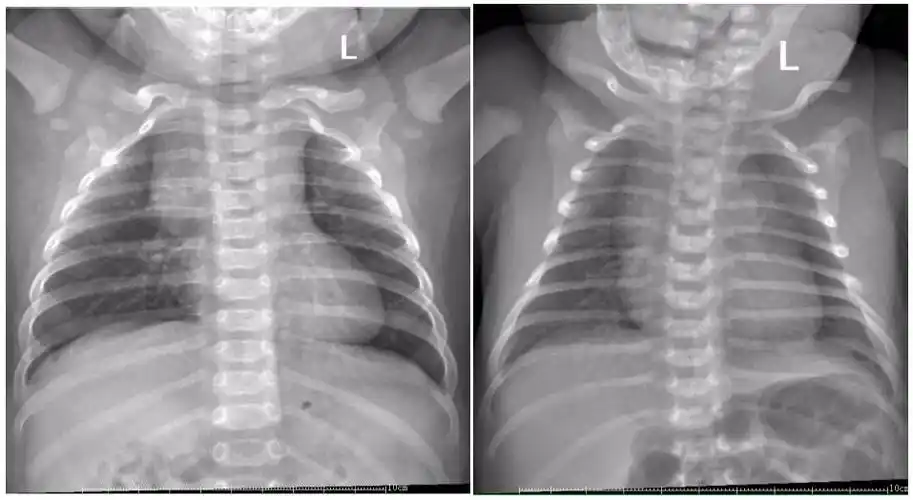

新生儿肺部常见疾病的x线诊断2 新生儿感染性肺炎 男,3天.